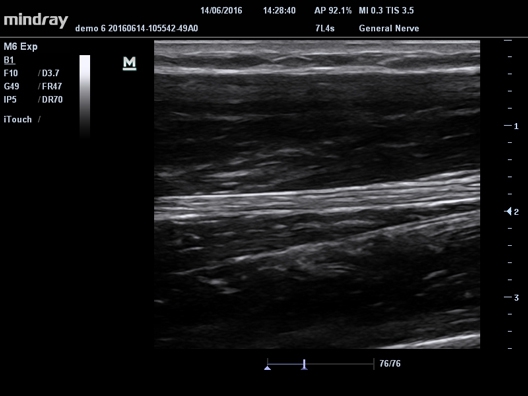

Mindray M-5 - это портативный цветной УЗИ-сканер с широким набором методов сканирования и модулем формирования панорамного изображения. Это устройство объединяет возможности современных стационарных УЗИ-систем и ноутбуков, обладает эргономичным тонким LCD-монитором диагональю 15 дюймов, встроенным аккумуляторным устройством и широким функционалом, что обеспечивает комфортную и эффективную работу.

Mindray M-5 стал популярным среди врачей, благодаря своему небольшому весу, всего 6 кг. Он идеально подходит для использования в скорой помощи и предоставления медицинской помощи на дому. Несмотря на то, что M-5 относится к среднему классу ультразвуковых сканеров, он не уступает конкурентам в своей категории по мощности и интеллектуальным возможностям.

При необходимости сканер может быть установлен на специальную тележку, что делает его стационарным. Это особенно актуально, если у вас есть только один диагностический кабинет, но требуется много мобильных сеансов.

• Nerve package Программы для регионарной анестезии